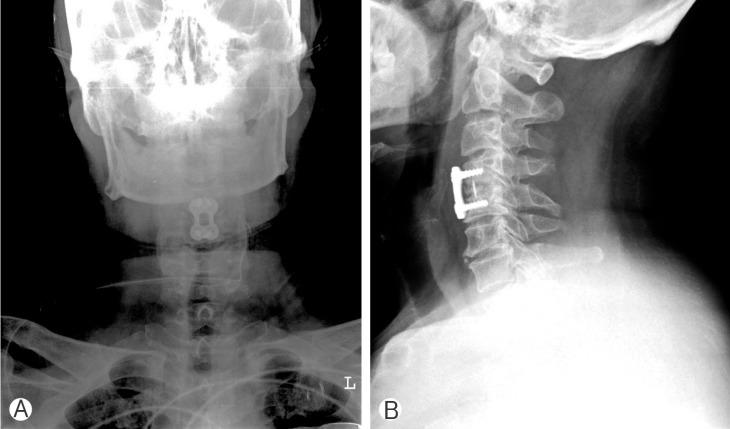

A total of 81 patients were enrolled for this study. Forty-five patients were included in a cervical plate group and the others were in stand-alone cage group. There was no statistical difference in pain score between the 2 groups. Segmental subsidence was observed in 7 patients (15.6%) in plate-assisted cervical fusion group, and 13 patients (36.1%) in stand-alone cage group. Segmental kyphosis was observed in 4 patients (8.9%) in plate-assisted cervical fusion group, and 10 patients (27.8%) in stand-alone cage group. There was statistical difference between the 2 groups.

本研究共纳入81例患者。45例患者纳入颈椎前路钢板组,其余患者纳入单纯椎间融合器组。两组间疼痛评分无统计学差异。颈椎前路钢板辅助融合组有7例患者(15.6%)出现节段下沉,单纯椎间融合器组有13例患者(36.1%)出现节段下沉。颈椎前路钢板辅助融合组有4例患者(8.9%)出现节段后凸畸形,单纯椎间融合器组有10例患者(27.8%)出现节段后凸畸形。两组间存在统计学差异。